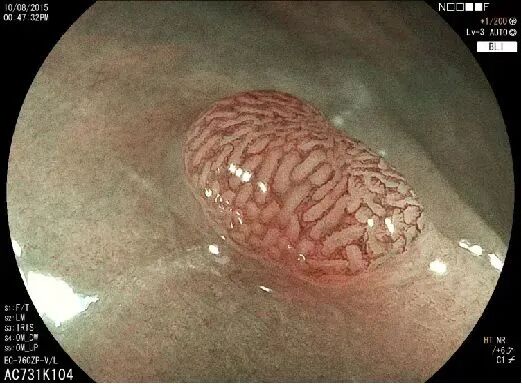

上高县中医院胃镜室引进了新一代富士Eluxeo Lite 6000高清电子胃肠镜。

富士Eluxeo Lite 6000高清电子胃肠镜系统称为内镜中的“福尔摩斯”,具有国际先进早癌诊断技术,相较于传统使用的白光内镜,呈像更清晰、更细微,可以一次性做到常规检查和精查。

富士6000拥有超强高清的视图及LCI、BLI特殊光染色,能够详细观察粘膜表层微血管以及微结构,可以更全面、更快速的发现早癌及其他消化道病灶,有效提高消化道早期肿瘤病变和炎性疾病的检出率,让消化道早癌无处遁形。